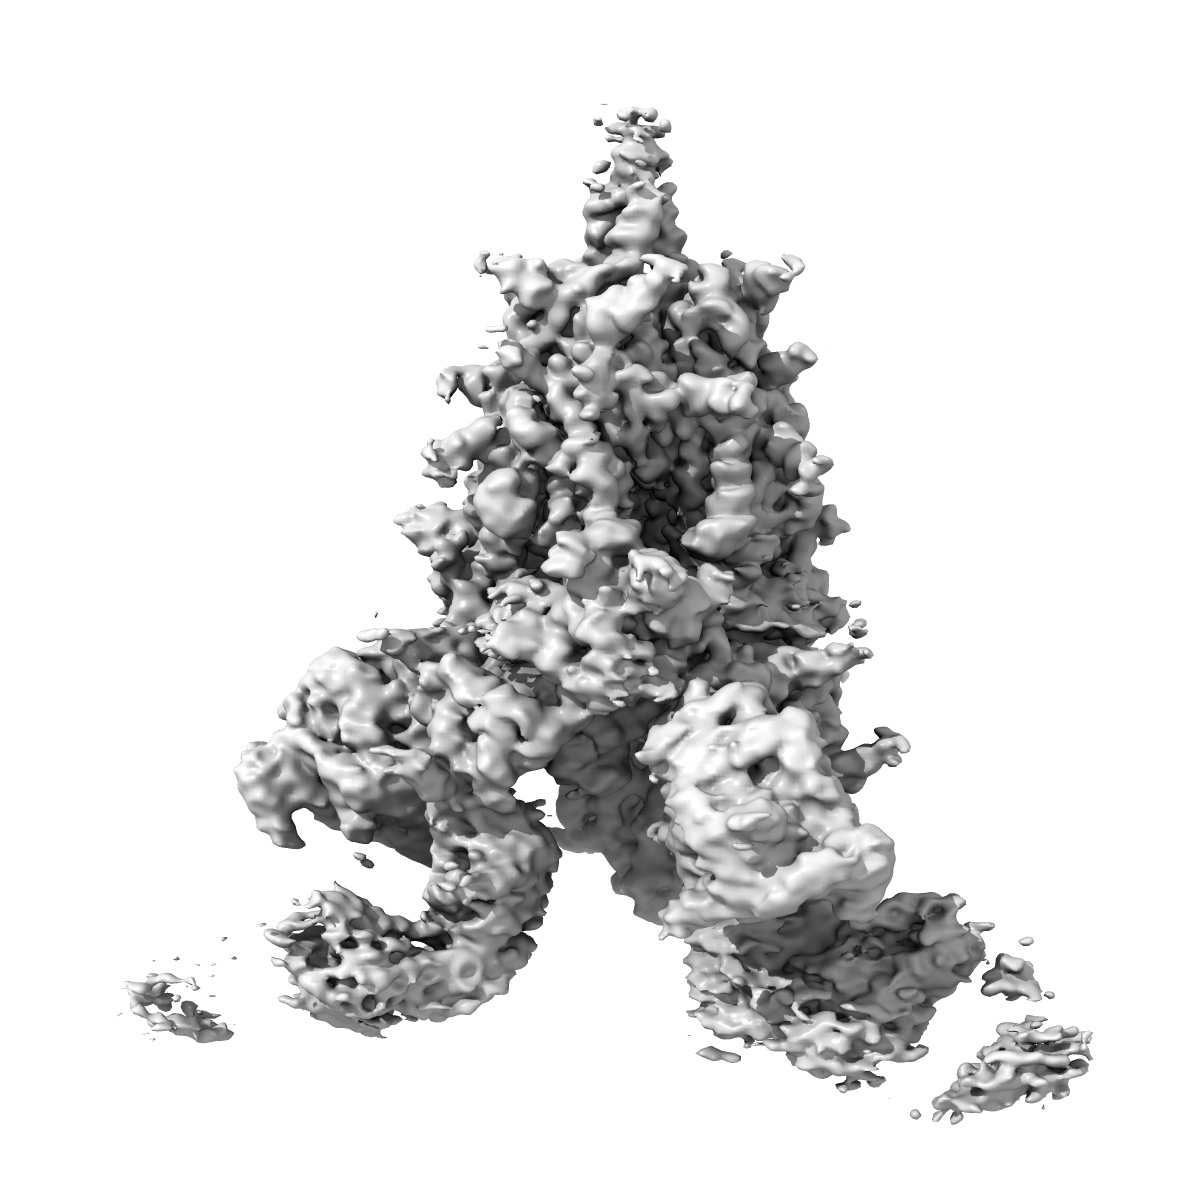

SARS-CoV-2 spike + IMCAS-123

Sample: Cryo-EM structure of SARS-CoV-2 spike + IMCAS-123

Deciphering a reliable synergistic bispecific strategy of rescuing antibodies for SARS-CoV-2 escape variants, including BA.2.86, EG.5.1, and JN.1.

Tong Z, Tong J, Lei W, Xie Y, Cui Y, Jia G, Li S, Zhang Z, Cheng Z , Xing X, Ma H , Deng L, Zhang R, Zhao X, Liu K, Wang Q, Qi J, Huang H, Song R, Su Z, Wu G, Lou J, Gao GF

(2024) Cell Rep , 43 , 114338 - 114338